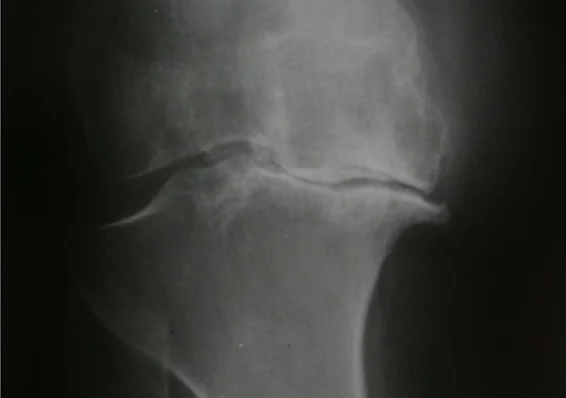

Pain, reduced function and impacts on a person’s ability to carry out their day-to-day activities can be important consequences of osteoarthritis. This can lead to changes in a patient’s mood, sleep and coping abilities. Visible changes on an x-ray don’t always reflect the symptoms of osteoarthritis experienced by patients; minimal changes can be associated with a lot of pain, or modest structural changes to joints can occur with minimal accompanying symptoms. Contrary to popular belief, osteoarthritis is not linked to ageing and does not necessarily deteriorate. There are a number of management and treatment options (both pharmacological and non-pharmacological) which we will cover.

Osteoarthritis is a condition that results from a loss of cartilage with subsequent remodelling of adjacent bone and subsequent inflammation. It is some of these changes in the joint structure that can then be seen on x-ray.